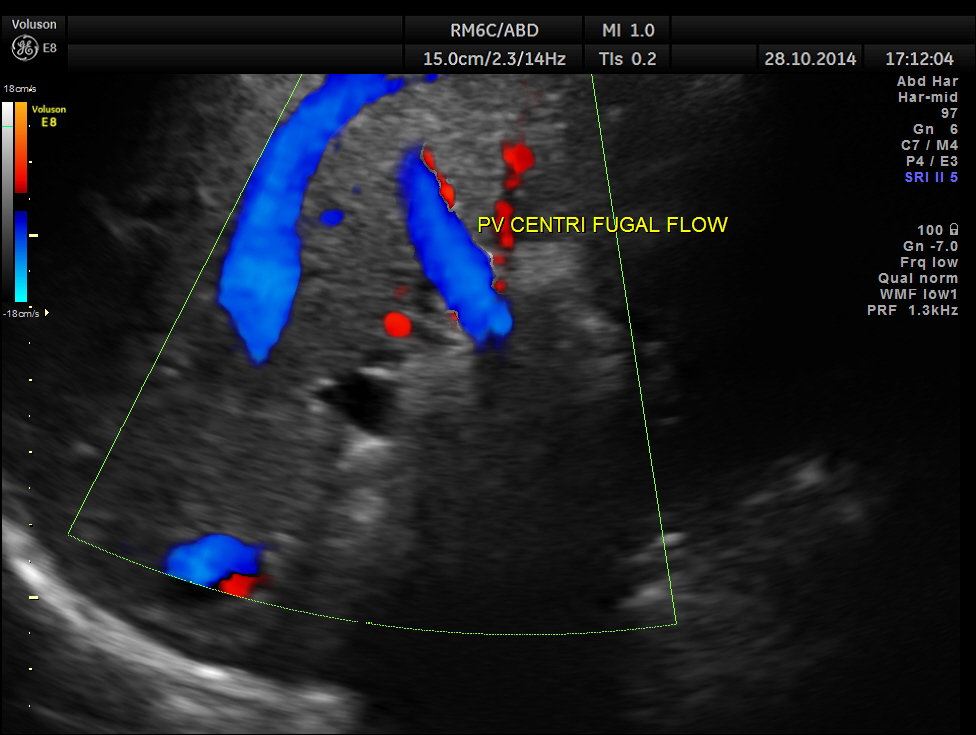

Main portal vein show flow reversal ( blue colour ) – centri-fugal flow suggestive of portal hypertension.